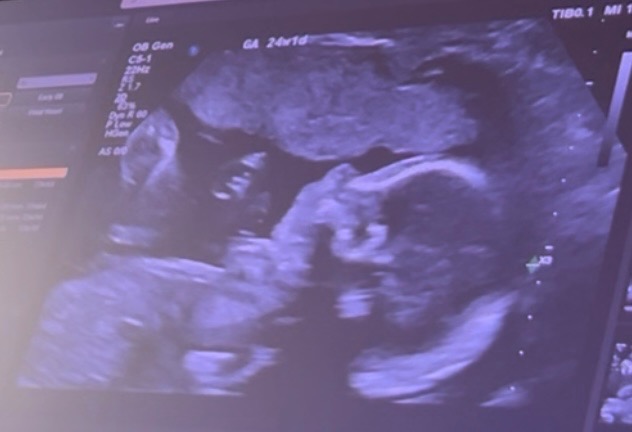

On October 29th, 2025 I walked into a routine 20th week ultrasound but with my excitement put to the side I was taken aback by the way things started taking a turn for the worse throughout the checkup, as I was laying there looking at my beautiful girls growth and admiring her little face when I would get glimpses of her they began the scan of her heart but to my surprise and concern the scan on her heart was taking longer then I remember as I just had a baby 8months ago and have had 3 before I didn’t recall it ever taking this long, my heart began sinking in my chest feeling so powerless and not having my questions answered with certainty was even worse, one ultrasound tech after the other walked in without clear understanding I was sent home with a heavy heart and a lot unanswered what ifs, an appointment was scheduled 2 weeks out to get an echocardiogram for further evaluation, the days couldn’t have gone by any quicker but November 3rd,2025 I walked in to that appointment with hope and faith that things weren’t as they seemed, the tech lays me down explained what she may be looking for and we proceed with the ultrasound she looks at the heart takes a few pictures stops and says there is definitely something wrong with the baby’s heart i am so sorry, let me finish up and I can get into more detail about what’s wrong, instant tears running down my face but keeping it together so she can get what she needs to finish the imaging, she concludes the ultrasound and begins to go more into depth about what she saw feeling weak by the news I get as much information as I can and walk out with a promised call from a pediatric cardiologist on Oahu, patiently waiting I receive the phone call and long story I was told my baby has

HLHS- Hypoplastic Left Heart Syndrom is a complex congenital heart defect where the left side of the heart, including the left ventricle, aorta, and aortic and mitral valves, is underdeveloped. This prevents the left side from properly pumping enough oxygen-rich blood to the body, which is often managed with a series of surgeries, starting shortly after birth. Without intervention, the condition is not survivable.

receiving such crippling news was devastating to me, i got myself together and began my research made appointments necessary so I that we could proceed with this process. I made an appointment for November 21st, 2025 so that I could head up to Oahu to meet the pediatric cardiologist and undergo another echocardiogram to see the progress of baby’s Heart growth, I went up had the echo done and proceeded to go upstairs with the doctor she sits me down and begins to explain the delicate nature of my daughter‘s congenital heart, defect, and what that meant for the remainder of the pregnancy long story short, she explains that I would need to fly off island in order for my daughter to survive after labor and delivery that she would need to undergo three major Hart surgeries with the first and second phase being the most critical and delicate because of infection and downtime to recover the first surgery could take up to nine hours and that between the first and second phase, the hospital would not be able to house us, but it was necessary to stay close for any complications that may occur away from the hospital. Receiving this information really took me back financially emotionally, and physically I wasn’t sure if I was ready, but with my daughter‘s best chances to survive in mind only, I began to make a decision on the hospital. I would be heading out to at around 32 weeks so I could be closely monitored and prepped for labor and delivery where from there I would get very little time with my newborn before she’s taken into the OR